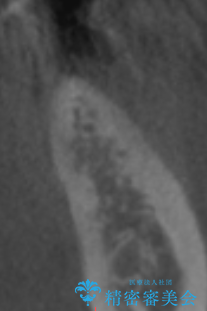

- 左下6番目の歯が欠損しており、インプラントで治療することとなりました。

骨の横幅が薄くなっており、インプラントを埋入するには骨幅が足りない状態でした。

まず最初に骨造成を行い、その後にインプラント埋入手術を行うこととなりました。

骨を増やすための手術が必要になるので、通常のインプラント治療より手術回数が一回多くなってしまうのがデメリットですが、将来的に安定したインプラントにするため、骨造成手術を前もって行いました。

しっかりとした骨幅を獲得し、理想的な太さのインプラントを埋入することができました。